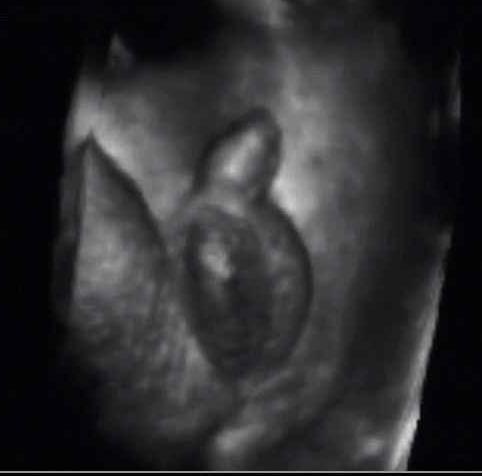

Bebek Cinsiyeti Kaçıncı Haftada Belli Olur Kadınlar Kulübü

Bebek Cinsiyeti Kaçıncı Haftada Belli Olur Kadınlar Kulübü.